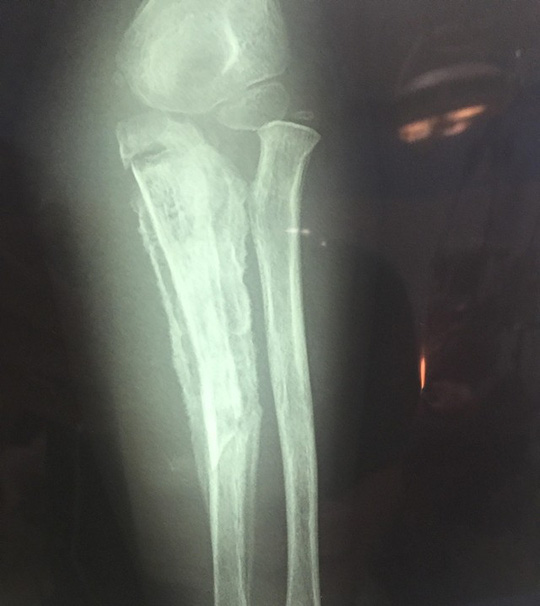

| Phim chụp X-quang cẳng tay cháu M. cho thấy cẳng tay bị gãy |

Bác sĩ Lê Tuấn Anh, Phó trưởng Khoa Chỉnh hình nhi, Bệnh viện Nhi Trung ương, cho biết khi được đưa đến bệnh viện, cẳng tay cháu M. có rò mủ, toàn bộ vùng cẳng tay trái sưng nề. Trên phim chụp X-quang thấy có hình ảnh viêm xương trụ, có 1 đoạn xương ở vị trí 1/3 giữa trên đã hoại tử, vùng khuỷu tay hạn chế gấp duỗi, các ngón tay co gấp, không duỗi được. Trong quá trình phẫu thuật, các bác sĩ đã tiến hành lấy bỏ ổ mủ, lấy bỏ đoạn xương trụ hoại tử dài 6 cm ở 1/3 giữa trên cẳng tay, bơm rửa ổ viêm xương, đồng thời đặt dẫn lưu và bất động cẳng tay bằng nẹp bột. Sau phẫu thuật, cháu M. được chỉ định dùng kháng sinh liều cao theo kháng sinh đồ. Hiện tại, bé M. đang được điều trị tại Khoa Chỉnh hình nhi.